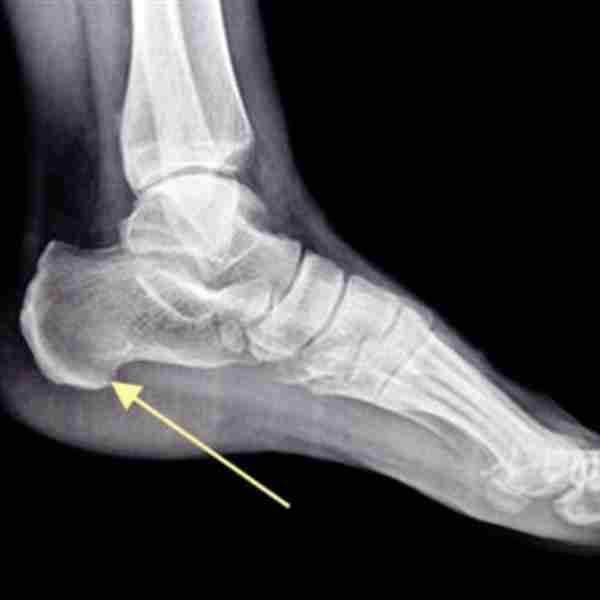

Le diagnostic de l'épine calcanéenne nécessite une consultation médicale approfondie, incluant potentiellement des radiographies et une échographie en première intention. Les causes incluent des traumatismes répétés au talon, l'obésité, des déformations du pied, une prédisposition génétique, ou encore des pathologies telles que la fasciite plantaire.